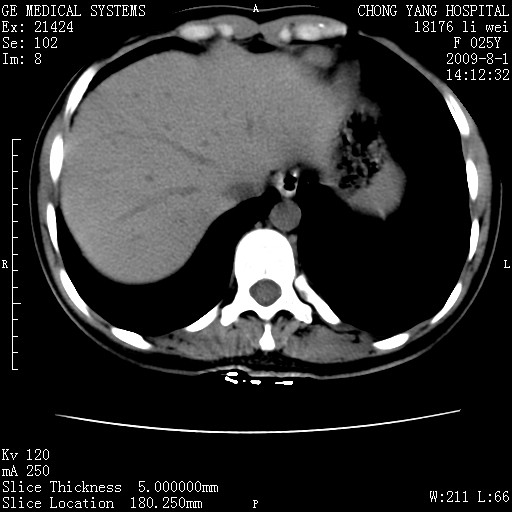

以下是引用pujunzhi在2009-8-1 20:23:00的发言:[br]胸椎旁及背部肌间良性病变,范围广,边界清,沿肌间生长,考虑淋巴管瘤、血管瘤,建议增强扫描。